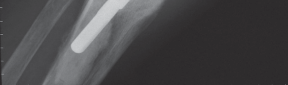

Thorough preoperative planning is mandatory to optimize outcomes and minimize intraoperative complications. The surgeon must obtain orthogonal radiographs of the affected knee to assess the status of the arthroplasty components. Component loosening, severe osteolysis, or malpositioning must be addressed concurrently with the extensor mechanism reconstruction.

Tibial Host Bed Preparation and Fixation

A corresponding trough is created in the host anterior tibia, slightly medial to the native tibial tubercle to optimize the Q-angle. The trough is undersized by 1 to 2 millimeters to ensure a rigid press-fit of the allograft bone block.

The allograft bone block is impacted into the host trough. Fixation is achieved using the previously placed cerclage wires or cables, which are passed around the proximal tibia or through transverse drill holes in the tibial metaphysis. Supplemental fixation with anterior-to-posterior cortical screws can be utilized to enhance rotational stability and resist the massive pull-out forces generated during knee flexion.